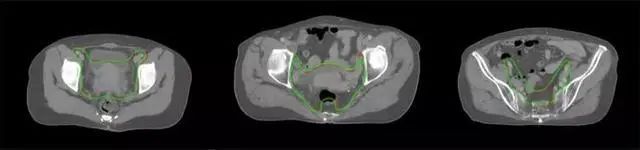

放射治療,簡(jiǎn)稱放療,是治療腫瘤主要手段之一,利用放射線破壞照射區(qū)(靶區(qū))的細(xì)胞,使腫瘤細(xì)胞停止分裂直至死亡,醫(yī)生通常把放射治療形象的比喻為“打靶”,放療前精準(zhǔn)勾畫腫瘤靶區(qū)范圍是腫瘤放射治療的關(guān)鍵步驟。傳統(tǒng)的靶區(qū)勾畫醫(yī)生會(huì)根據(jù)患者多張CT、MRI影像片憑借經(jīng)驗(yàn)進(jìn)行,比較耗時(shí),治療的病人數(shù)量也有限,且靶區(qū)勾畫缺少行業(yè)統(tǒng)一的規(guī)范和標(biāo)準(zhǔn),無(wú)法達(dá)到同質(zhì)化,勾畫精確度不理想。

技術(shù)原理

基于深度學(xué)習(xí)人工智能的放療靶區(qū)智能勾畫技術(shù)和自動(dòng)計(jì)劃技術(shù),基于全面的市場(chǎng)調(diào)研和臨床專業(yè)意見(jiàn),采用獨(dú)創(chuàng)的基于小樣本量的人工智能算法,實(shí)現(xiàn)放療靶區(qū)和危及器官的快速全自動(dòng)勾畫。

產(chǎn)品優(yōu)勢(shì)

縮短至幾分鐘內(nèi)便可完成,大幅提升了放療效率,且人工智能平臺(tái)完成的靶區(qū)勾畫可基本滿足臨床醫(yī)生需求,專家只需審核時(shí)細(xì)微調(diào)整,可顯著提高靶區(qū)勾畫的規(guī)范化及精準(zhǔn)度,讓放療智能化,標(biāo)準(zhǔn)化??筛采w食管癌、鼻咽癌、直腸癌、宮頸癌、肺癌等多種病種。